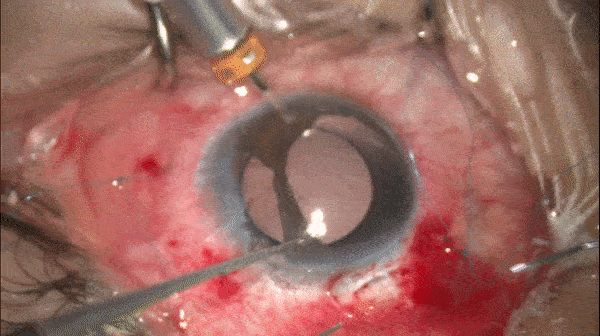

再次采用上述方式在对侧襻上完成改良cow-hitch knot

开睑器怎么用术说睛彩 | 金海鹰教授:使用8-0缝线的无巩膜瓣人工晶体固定手术_https://www.jmylbn.com_新闻资讯_第7张